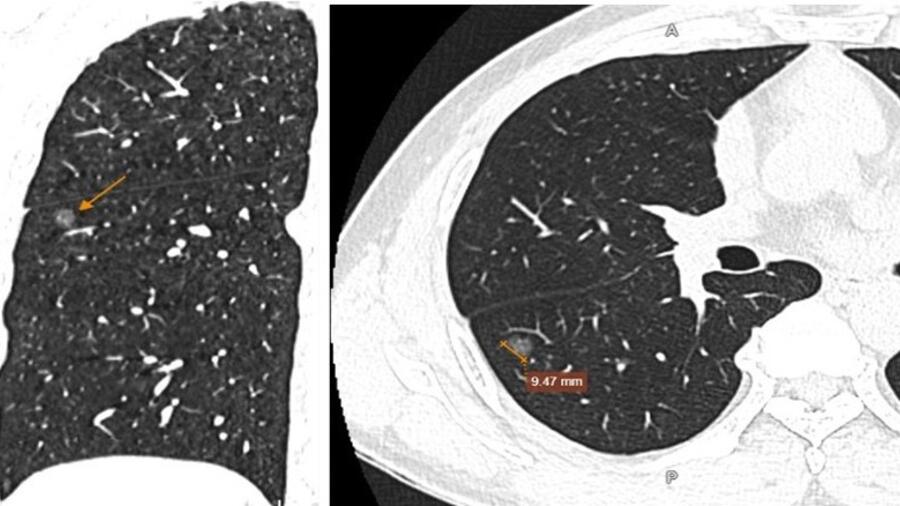

Hình ảnh nốt kính mờ phân thùy S6 phổi phải đường kính 9,5mm, kèm một số nốt rải rác nhu mô hai phổi

Bệnh nhân được chỉ định làm các xét nghiệm và chẩn đoán hình ảnh cần thiết. Kết quả chụp cắt lớp vi tính (CT scan) cho thấy, hình ảnh nốt kính mờ phân thùy S6 phổi phải đường kính 9,5mm, kèm một số nốt rải rác nhu mô hai phổi, dày trung thất, dày màng phổi vùng đỉnh một bên, xơ vữa vôi hóa cung động mạch chủ, thoái hóa vài đốt sống ngực.